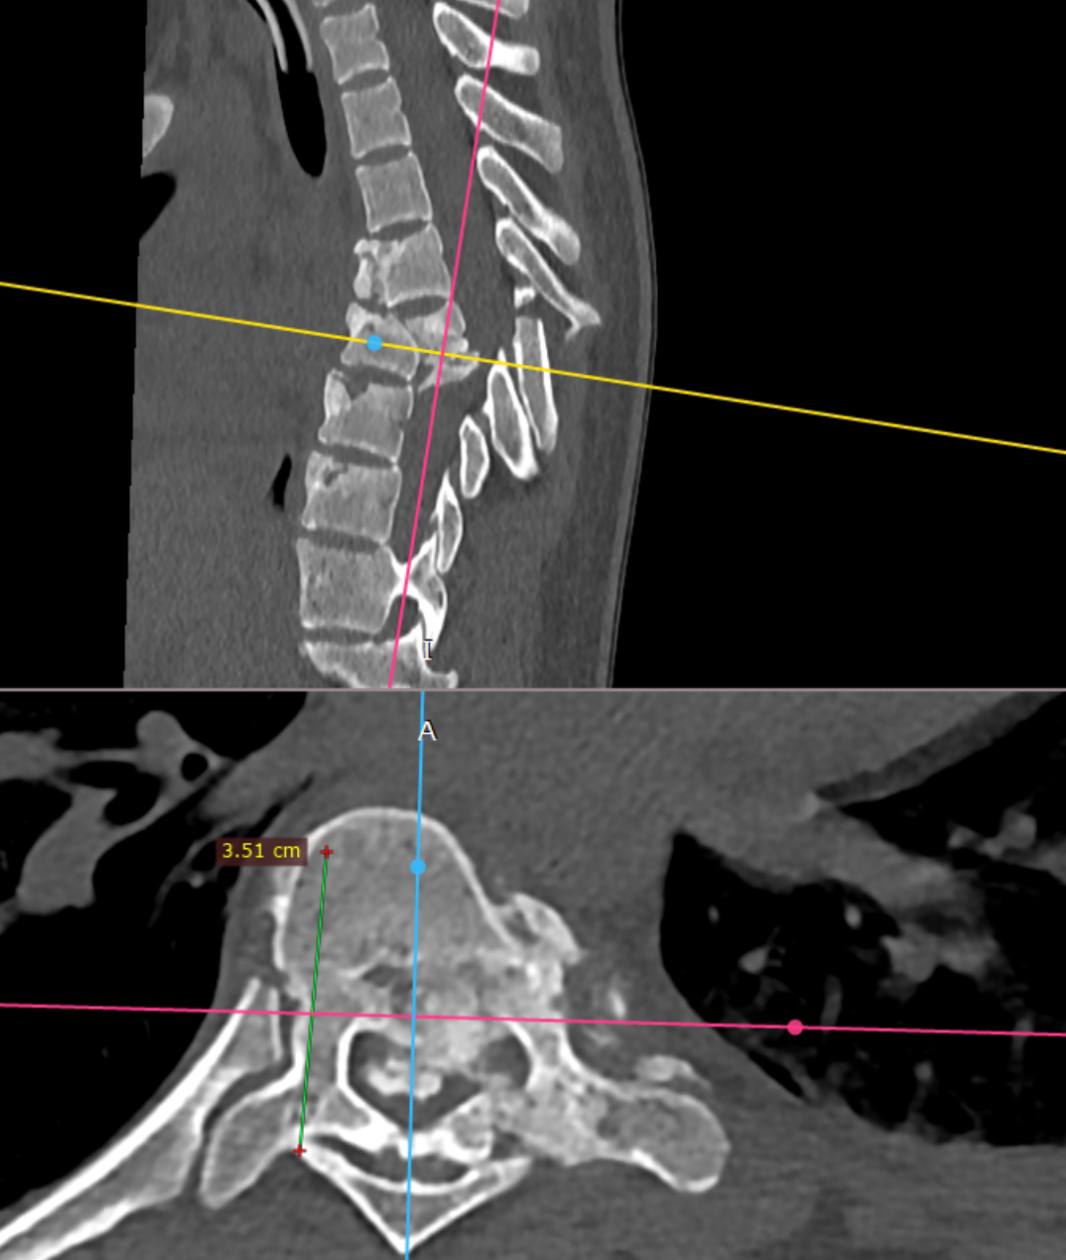

После стабилизации состояния и разрешения инфекционных осложнений девочку перевели в Новосибирский НИИТО для операции на позвоночнике. Хирурги столкнулись со сложнейшим случаем спондилоптоза — смещением позвонка с разрушением.

Операция длилась около 9 часов. Спинальные хирурги провели корригирующую вертебротомию — удалили часть поврежденного позвонка, исправили деформацию и зафиксировали позвоночник специальной металлоконструкцией. Во время операции врачи обнаружили, что дуральный мешок цел и пульсирует, что дает надежду на восстановление неврологических функций.